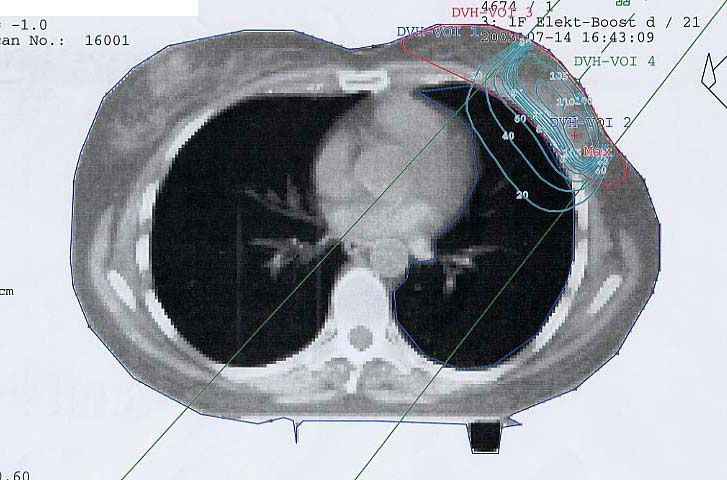

Mammakarzinom: Bestrahlungsplan

Einführung aktuelle Bilder - Einführung Bestrahlungspläne - Einführung Demonstration